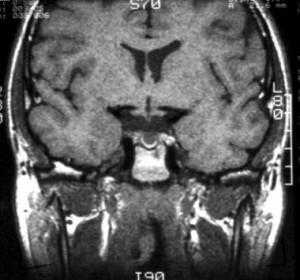

МРТ: киста кармана Ратке. На Т1-взвешенном сагиттальном изображении, полученном до введения контраста, заметно четко очерченное образование в области турецкого седла - с распространением в супраселлярную цистерну. Отмечается гомогенно высокая интенсивность сигнала в образовании по сравнению с паренхимой головного мозга.

Т1-взвешенное сагиттальное изображение, полученное до контрастного усиления: видна хорошо определяемая киста в зоне турецкого седла, изоинтенсивная спинно-мозговой жидкости. Отмечается соответствующая норме высокая интенсивность сигнала задней доли гипофиза сзади.

На Т1-взвешенном корональном изображении она видна рамером чуть менее сантиметра в центральной части турецкого седла. Слегка гиперинтенсивна по сравнению со спинно-мозговой жидкостью.

На этом Т2-взвешенном изображении она изоинтенсивна спинно-мозговой жидкости.

Крупная гиперинтенсивна по сравнению со спинно-мозговой жидкостью на аксиальном протонно-взвешенном изображении. Отмечается расширение турецкого седла с латеральным отклонением чуть заслоненной, но проходимой кавернозной частью внутренней сонной артерии.